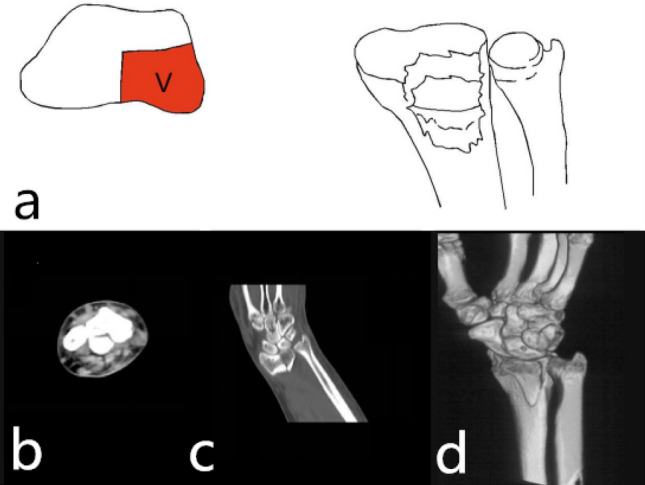

Single dorsal part fracture (1-D): Separate dorsal part fracture was not common in type 1. It was 2-DV type fracture that the fracture involved both the dorsal and palmar parts. It was a 2-DR type fracture that the fracture involved both the dorsal and radial parts. Separate dorsal part fracture (type 1-D) was characterized by a dorsal fracture of the cranial fossa articular surface or combined with a fracture of the dorsal articular surface of the scaphoid fossa. The articular surface and dorsal cortex were comminuted fractures. It was prone to cause subluxation or dislocation of the wrist. The mechanism was wrist dorsiflexion injury, and the only surgical approach was the dorsal approach with the dorsal plate fixation. Poor restoration and fixation of the dorsal column fracture resulted in malunion, which eventually caused a decrease in the anatomical compatibility of the radial wrist joint and a malunion of the radial sigmoid notch (Fig. 2).

Figure 2.

Distal radius fracture 123 classification A1.